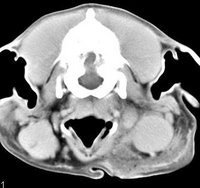

imágenes de TC en el perro | ||||||||||

ejemplo de imágenes de TC en el perro. Nótese la celulitis en la región parotídea izquierda | ||||||||||